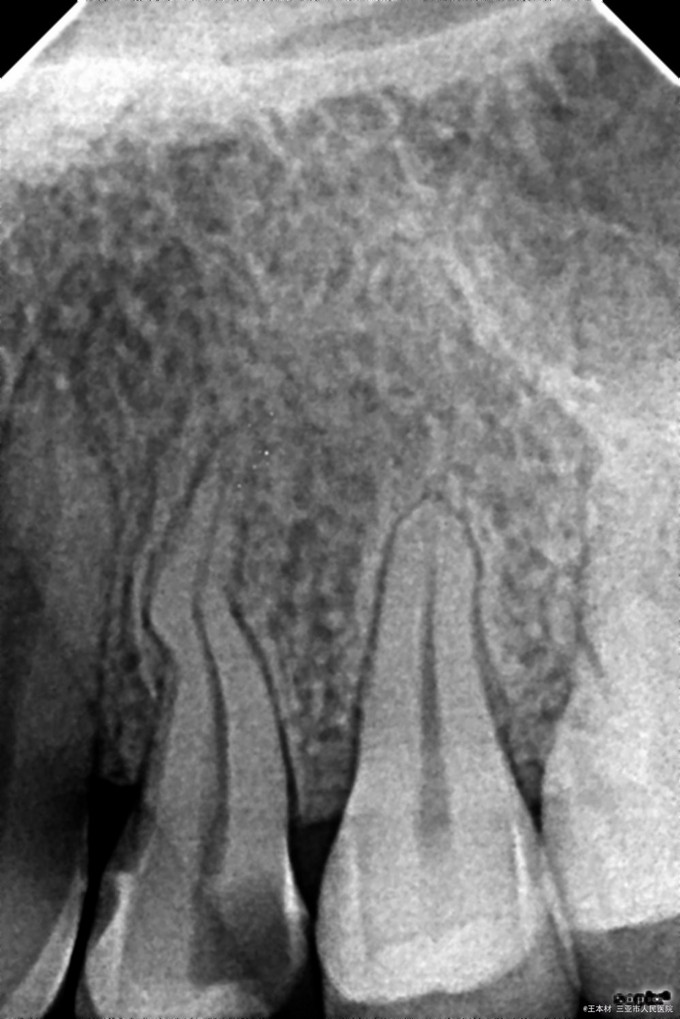

检查:患者22岁,24#远中邻颌面暂封材料,叩痛(+/-),松动度无,根尖部扪诊,压痛(-),牙髓活力冷测试无反应,余未见明显异常。 辅助检查:术前X线片示:24#根管中下1/3弯曲呈S形,牙周尚可,余未见明显异常。

诊断:24#急性牙髓炎 处置:24#调咬合,去暂封,取失活,去净腐质,髓室预备,暴露髓室底,根管口探查,GG钻(1-3#)扩大根管口,拔髓,根管探查疏通,根管预备至:PWL=16.0,40#,根尖定位仪根管长度测量,WL=B:19.5mm,P:19.0mm,均35#,参照点为平各自牙尖,EDTA凝胶,0.7%NaClO冲洗,棉捻干燥,CP棉球,ZOE简单充填。 医嘱:全身抗炎阿莫西林,治疗其间勿用患侧咀嚼硬物,5日后复诊,不适随诊。 5日后复诊如下: 主诉:患牙无明显异常。 检查:24#封物完好,髓室内清洁,叩诊叩痛(-),棉球无异味,余无明显异常。 处置:24#去暂封,取棉球,NaClO冲洗,棉捻干燥,牙胶尖+氢氧化钙碘仿糊剂根管充填,玻璃纤维桩,3MZ350树脂修行充填。 医嘱:2小时后使用患侧进食,择期冠修复,随诊。